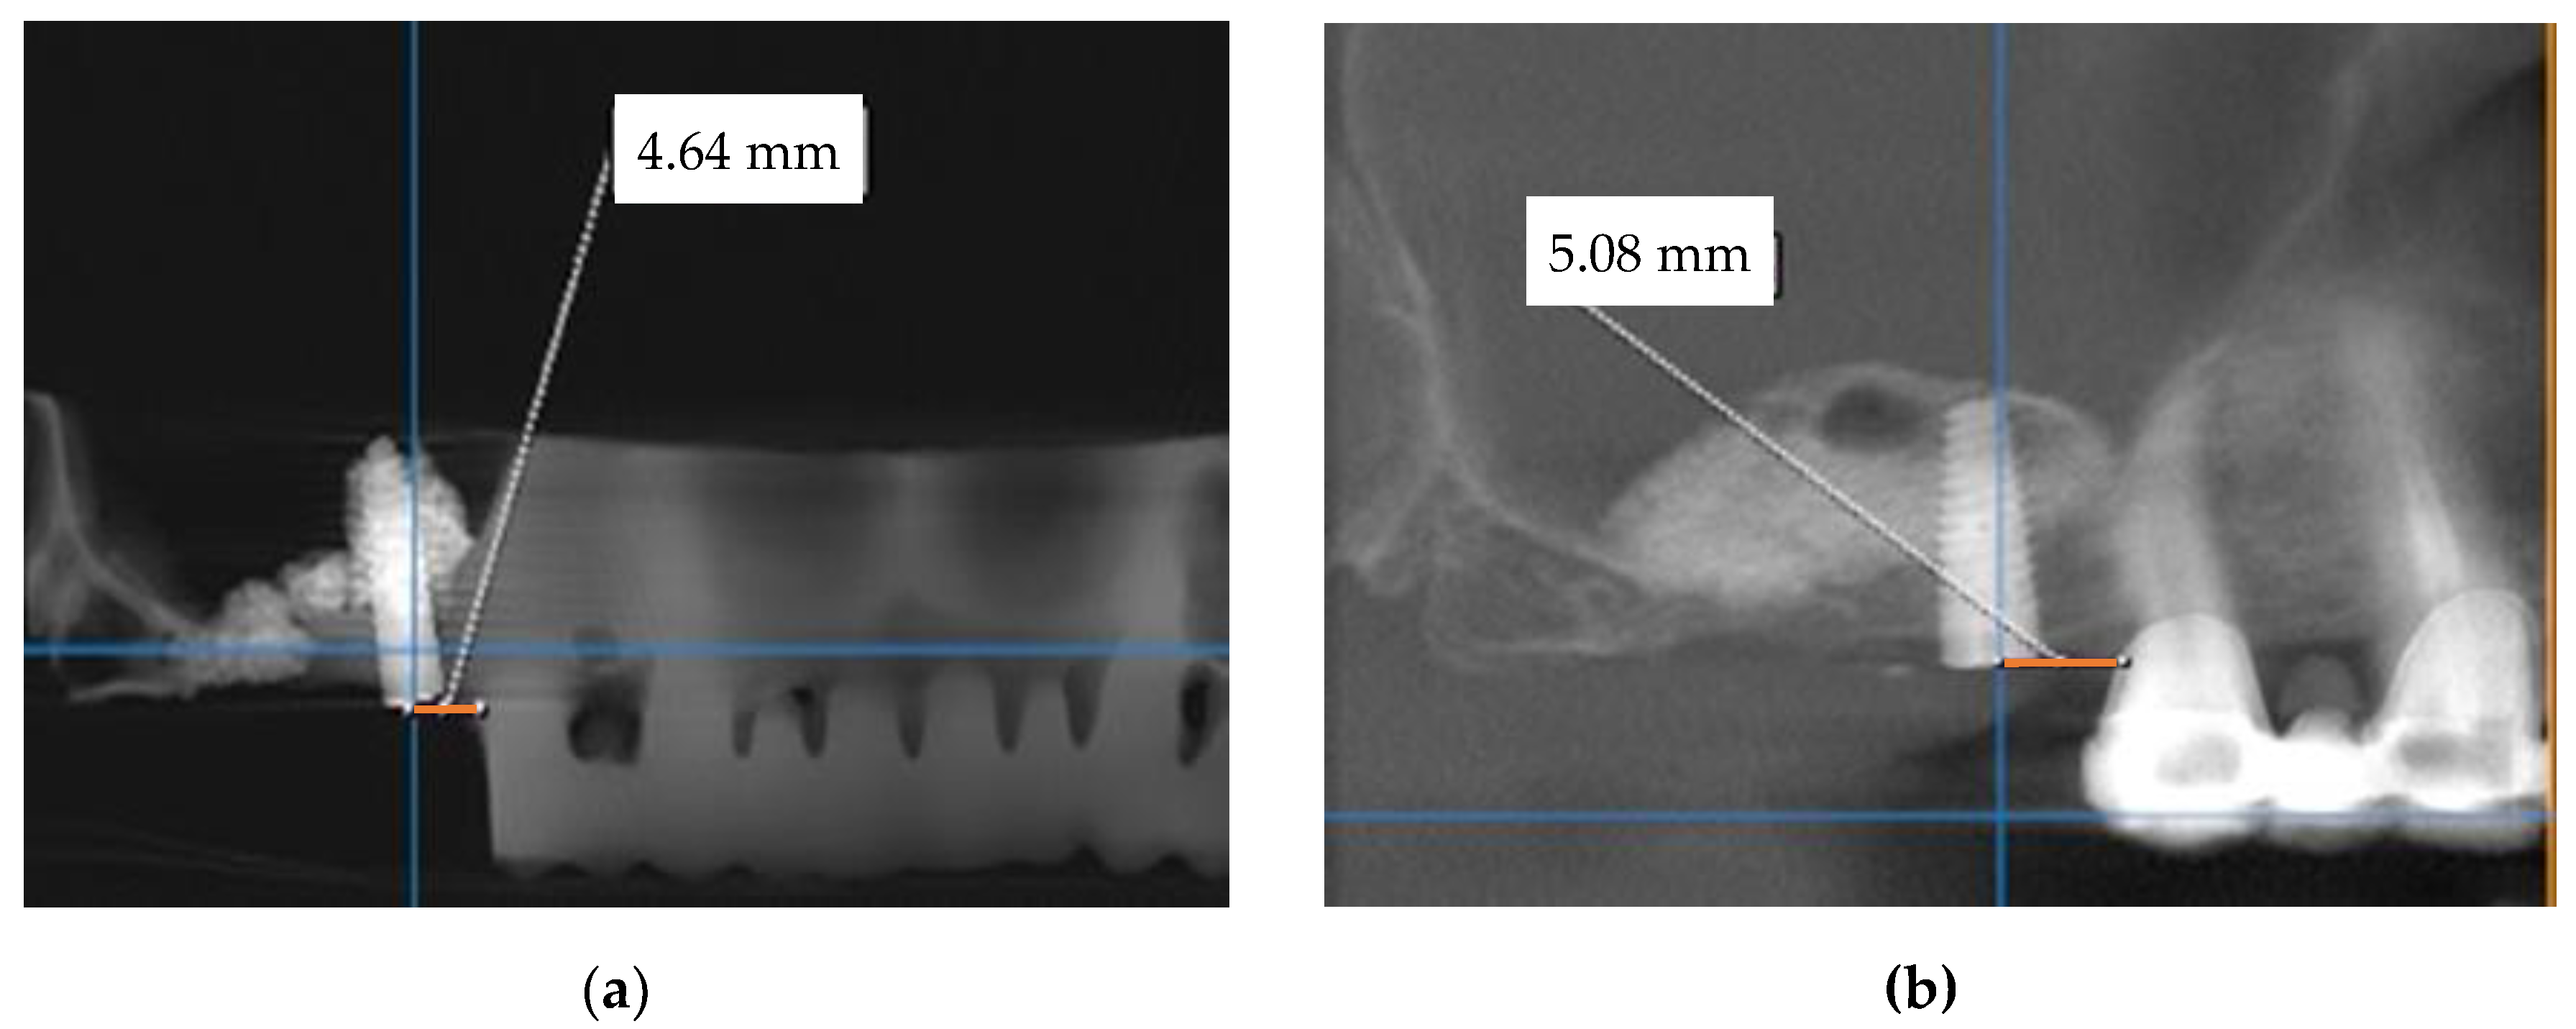

In this first step, a CBCT scan of the maxilla was performed to evaluate the bone anatomy and confirm the absence of the maxillary sinus pathology (Figure 2).

Figure 2. Cross-sectional CBCT views corresponding to: (a) the 16 with a bone height of 5.02 mm; (b) the 17 with a bone height of 2.65 mm and insufficient crestal width.